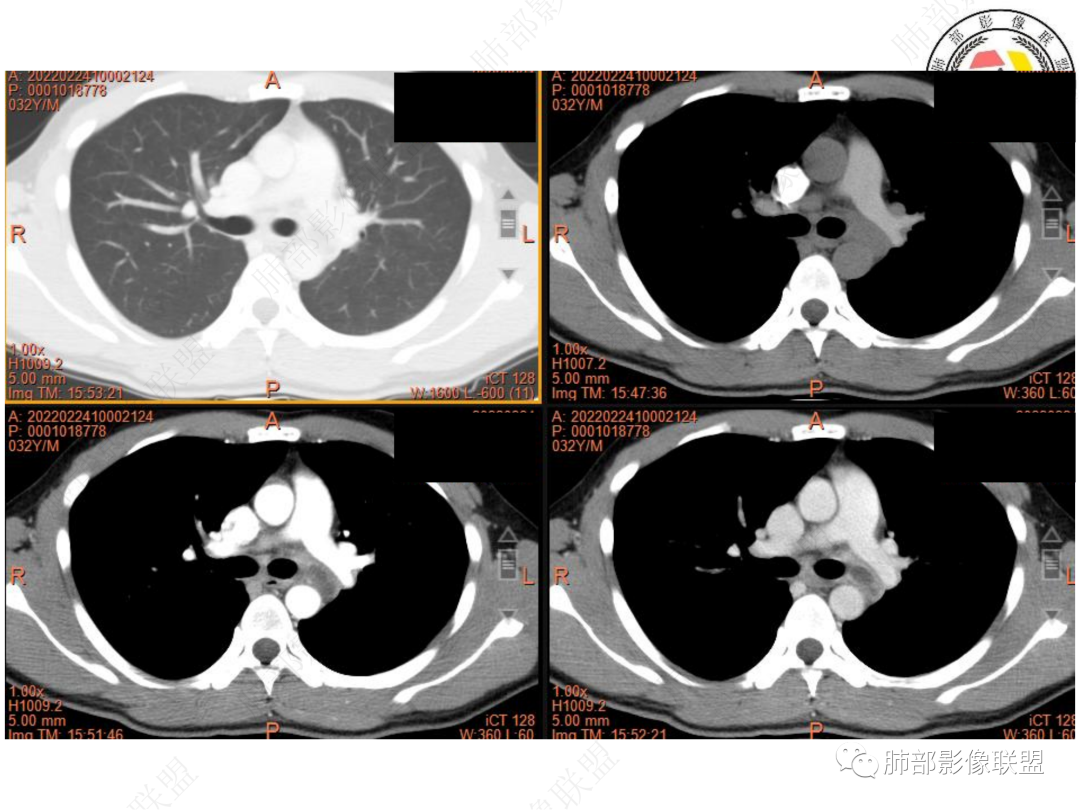

1. 青年男性,偶然发现左肺下叶结节影,左肺门及纵隔内多发淋巴结肿大,并坏死。

2. 肿瘤标志物及结核相关检查均为阴性。

3. CT示左肺下叶背段孤立实性密度结节影,边缘比较清楚光滑,总体呈现膨隆感,未见分叶毛刺,少张力,部分层面病灶边缘呈现较清楚磨玻璃样密度影,并于磨玻璃影病灶内可见多发小空泡,未见钙化或空洞,增强后病灶显示不均匀强化,未见低密度液化区。未见卫星病灶。

左肺门及纵隔内多发淋巴结肿大,大部分淋巴结显示融合,强化不均匀,内见低密度区,疑液化坏死。纵隔内淋巴结部分周围脂肪间隙不清晰。大血管及左肺主支气管未见受侵改变。